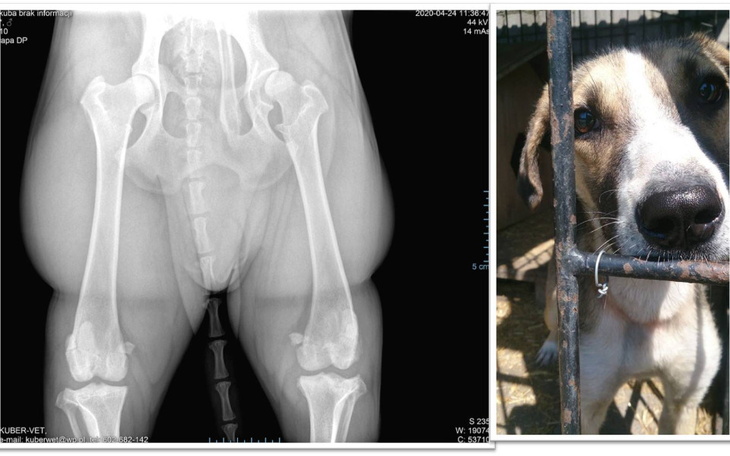

W ciągu kilku miesięcy wrócił do formy, pokazał nam jakim cudownym jest psem- kochającym, wpatrzonym w wolontariuszy jak w obraz. Jednak pech go nie opuszczał ...Kubuś zasiedział się w przytulisku na długie miesiące...W tym roku zauważyłyśmy, że zaczął poważnie kuleć na lewą tylną łapkę. Nie spodziewałyśmy się nawet, że diagnoza będzie tak poważna. Kubuś ma dysplazje lewego stawu biodrowego- schorzenie to polega na nieprawidłowej budowie głowy kości udowej i panewki miednicznej, skutkującej ich niedokładnym dopasowaniem. To z kolei powoduje nawracające stany zapalne i wiąże się z dalszym uszkadzaniem stawu. Operacja jest niezbędna. Kubuś bardzo cierpi przy każdym ruchu- nie może biegać, skakać, długie spacery sprawiają mu coraz większą trudność.

Kilka dni temu konsultowałyśmy Kubusia u dobrego ortopedy Pana dr n.wet. Tomasza Szczypki. Pan doktor podejmie się operacji biodra, wskazał także na konieczność wzmocnienia stawów kolanowych.